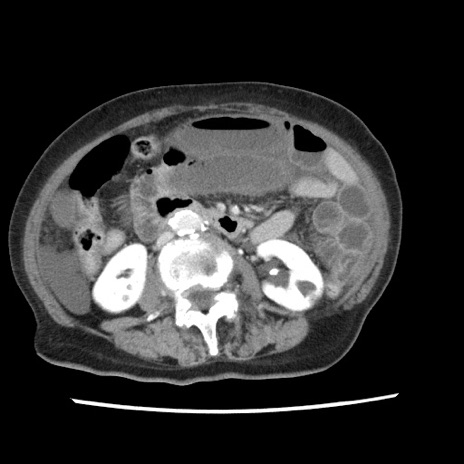

冠状断像

【症例】80歳代女性

【主訴】腹痛

【現病歴】8時間前から腹痛あり来院。

【既往歴】糖尿病、脂質異常症、子宮体癌にて子宮全摘術

【身体所見】意識清明・会話良好だが腹痛で苦悶様、全腹部にわたって反跳痛と圧痛あり

【データ】WBC 13600、CRP 0.14、LDH 224、CK 90